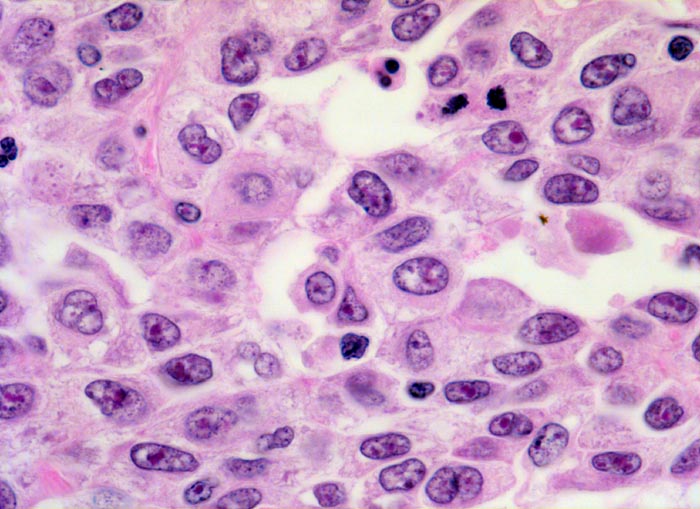

Urothelkarzinom

Solider Tumorzellverband. Scharf begrenzte stark polymorphe Tumorzellen mit reichlich Zytoplasma und ausgeprägten Kernatypien. Die entrundeten Kerne enthalten vergrösserte eosinophile unregelmässig geformte Nukleolen. Das Chromatin ist vergröbert. Zwei Mitosen.

Makrohämaturie. In der Harnblasenspülflüssigkeit werden Urothelien mit schweren Kernatypien vereinbar mit Urothelkarzinom nachgewiesen. Zystoskopisch kommt in der Hinterwand ein ulzerierter Tumor zur Darstellung. Die bioptische Abklärung ergibt Anteile eines wenig differenzierten Urothelkarzinoms mit ausgedehnten Nekrosen.

Gelegentlich enthalten kleine Biopsien aus einem Tumor lediglich nekrotische Tumoranteile. In solchen Fällen kann meist keine sichere Diagnose gestellt werden, da unter anderem die Kernbeurteilung als wichtiges Malignitätskriterium bei epithelialen Tumoren nicht möglich ist.